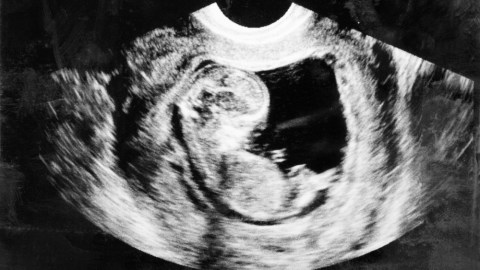

The new IVF technique is controversial because it involves the creation of what is colloquially known as a “three-parent embryo” – much to the chagrin of stem cell biologists.

Even though a sperm contains mitochondria, it does not contribute any to the embryo, meaning all the embryo’s mitochondria come from the mother’s egg.* Thus, if a woman has a mitochondrial disease, an embryo has essentially a 100% probability of inheriting the disorder. To prevent this, an egg with healthy mitochondria is required. And that’s where the “third parent” comes in.

If a healthy woman donates her egg, scientists can remove its nucleus (which contains most of the cell’s DNA) and replace it with the nucleus extracted from the mother’s egg. The resulting egg contains nuclear DNA from the mother and healthy mitochondria from the donor – i.e., the “third parent.” The new egg can then be fertilized and implanted into the mother.